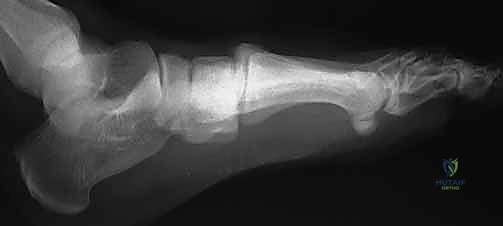

تتكون المفاصل الرسغية المشطية الثلاثة الإنسية (الداخلية) من العظمات المسمارية الإنسية والمتوسطة والوحشية، التي تتمفصل مع قواعد الأمشاط الأول والثاني والثالث.

في المقطع العرضي، تشكل هذه العظام شكلاً شبه منحرف فريدًا، مكونة ترتيبًا مقعرًا من الناحية الأخمصية (السفلية)، يشبه إلى حد كبير القوس الروماني الكلاسيكي في الهندسة المعمارية. توفر هذه البنية العظمية المتأصلة ثباتًا كبيرًا للقدم وتسمح لها بتحمل أضعاف وزن الجسم.

يُعتبر عظم المشط الثاني هو "حجر الزاوية" (Keystone) المطلق لهذا القوس؛ فهو يقع محشوراً بين العظمات المسمارية الإنسية والوحشية في المستوى المحوري، ويقع في قمة القوس في المستوى الإكليلي. إن ثبات هذا العظم (المشط الثاني) حاسم لمركب منتصف القدم بأكمله. أي إزاحة ولو بمليمترات قليلة في هذا المشط تؤدي إلى انهيار القوس بأكمله.

2. التصوير بالأشعة السينية (X-Rays) مع تحميل الوزن

الأشعة السينية العادية قد لا تظهر الإصابة إذا لم تكن العظام مزاحة بشكل كبير. السر يكمن في طلب أشعة سينية أثناء وقوف المريض وتحميل وزنه على القدم المصابة (Weight-bearing X-rays).